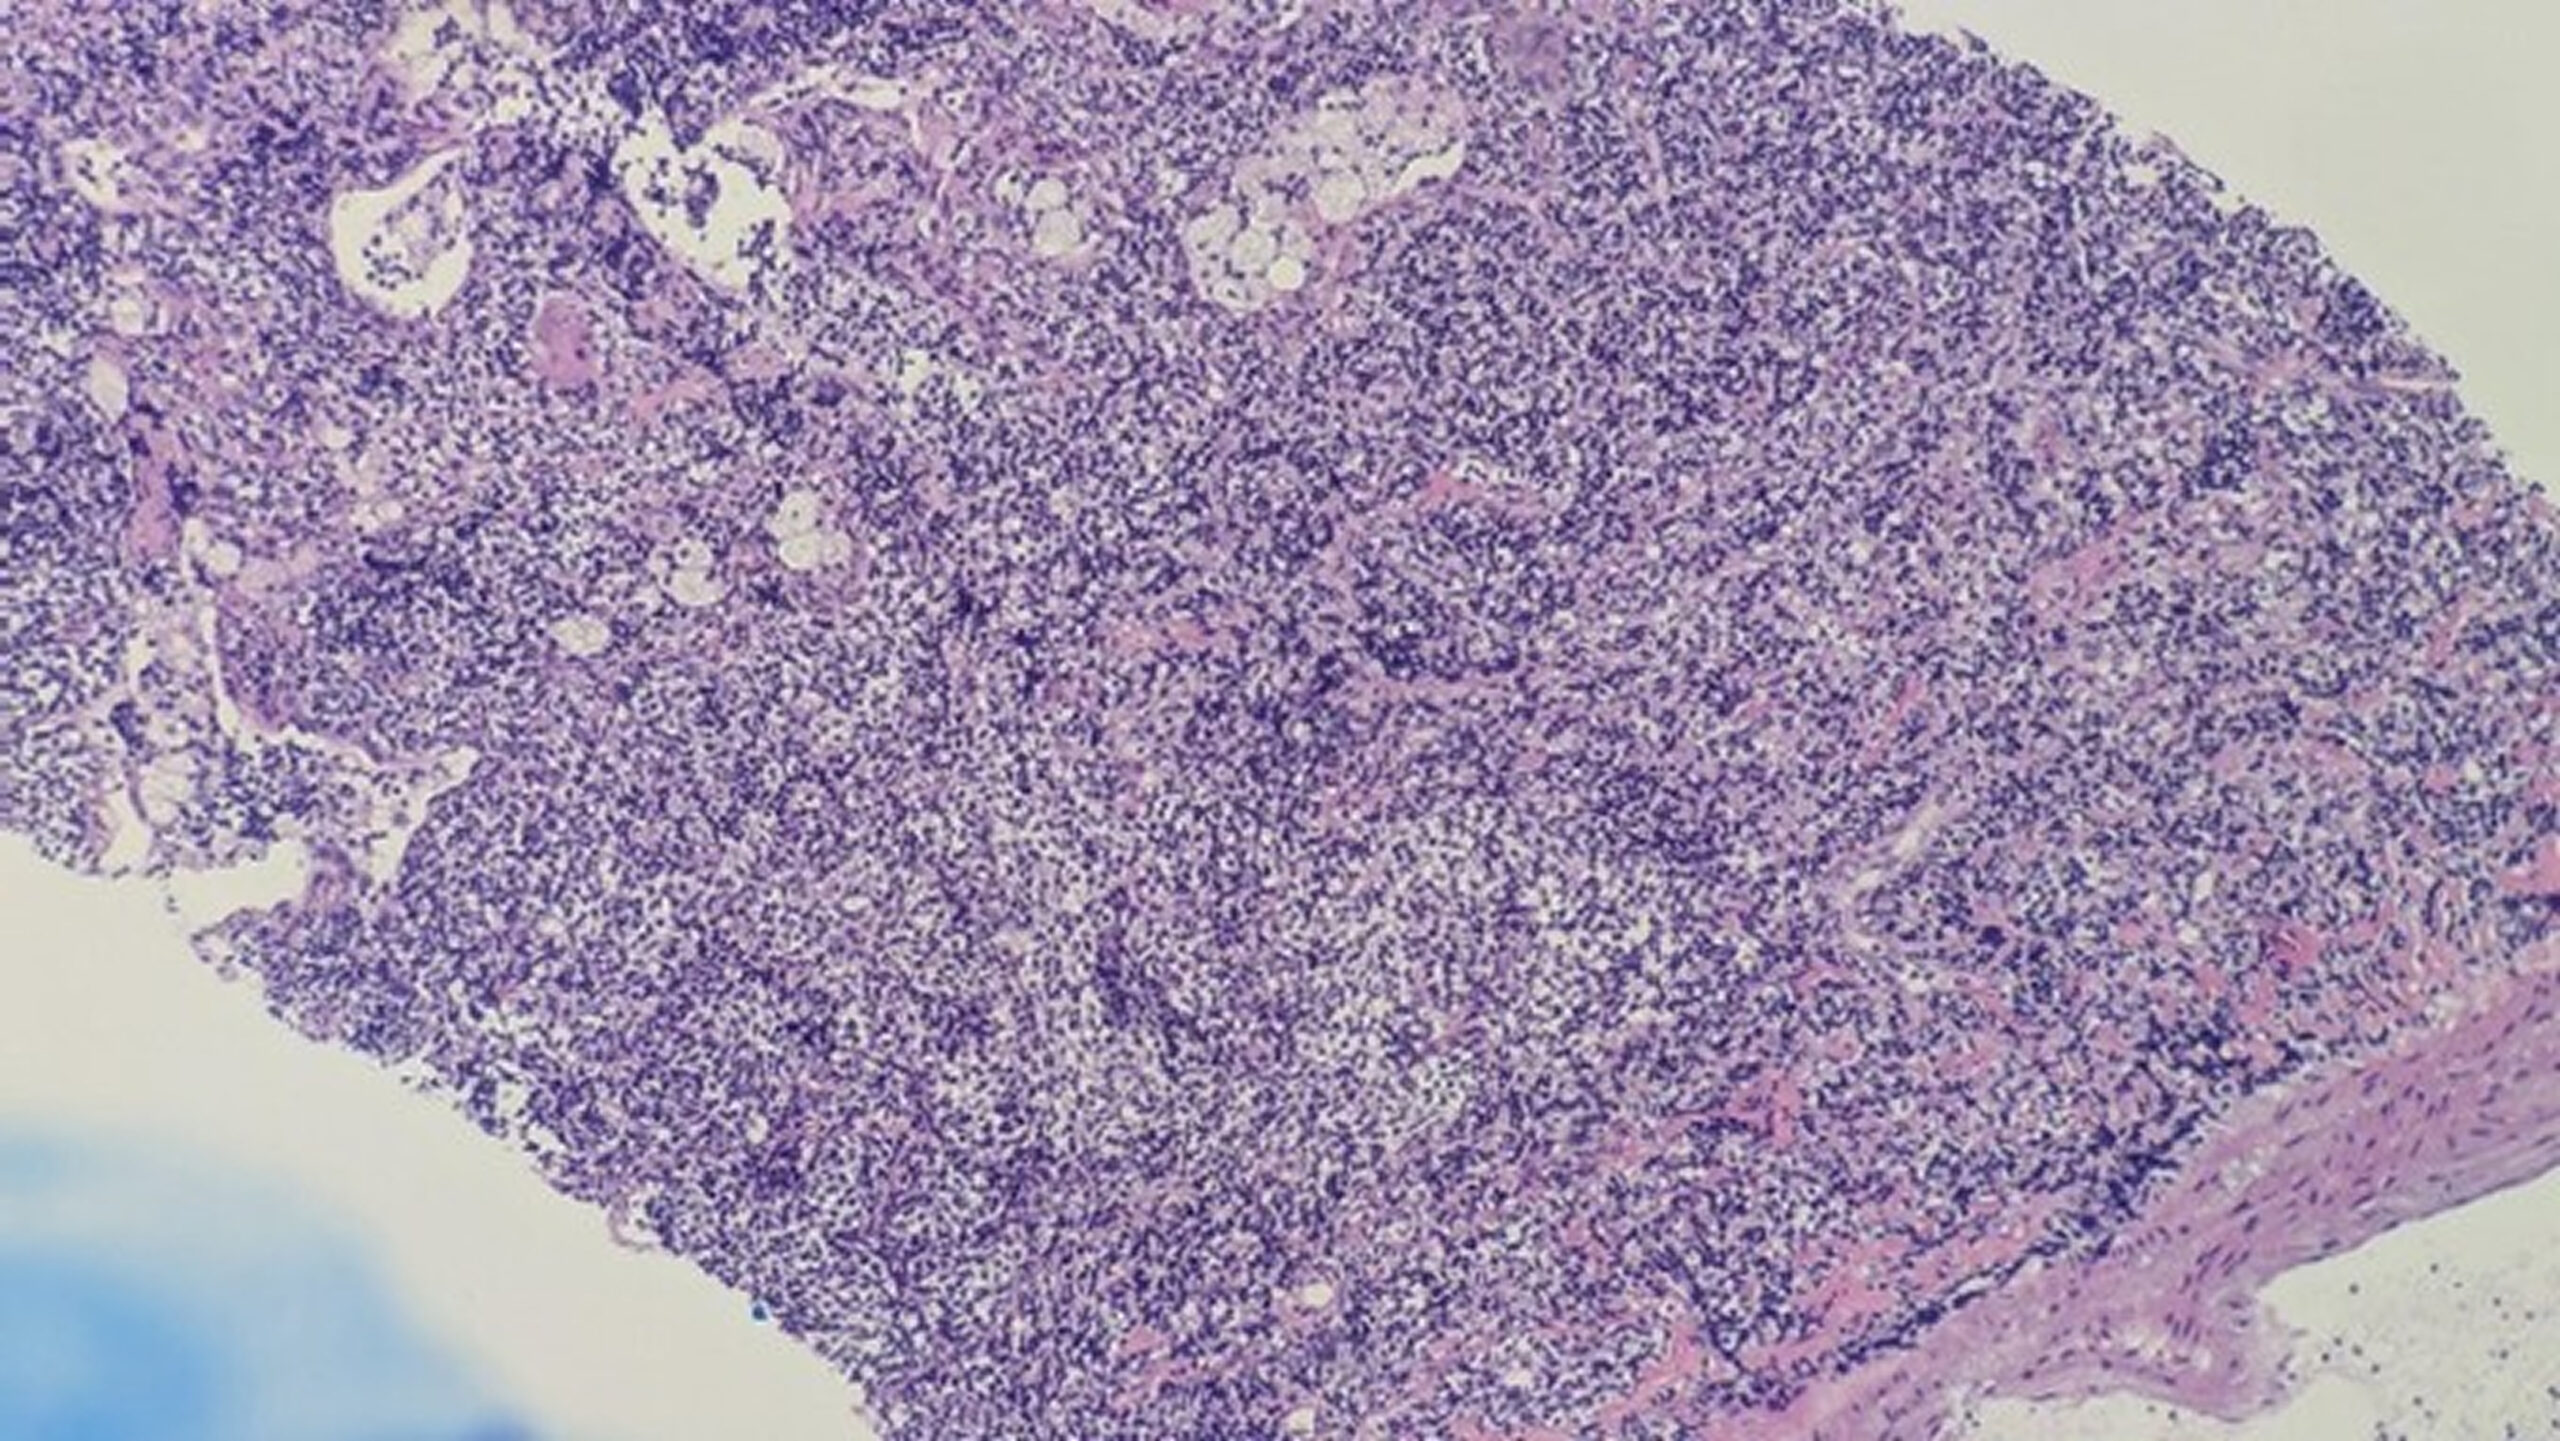

There was no indication of cancer in the first CT-guided lung biopsy, which showed a heterogeneous lymphocytic infiltrate. Due to persistent symptoms and unchanged imaging, a multidisciplinary team (MDT) recommended a repeat biopsy. The second CT-guided biopsy demonstrated malignant lymphoid cells diffusely positive for leukocyte common antigen (LCA), CD20, Pax5, Bcl2, and CD10, with scattered Bcl6 positivity (Figures 3 and 4). These findings were consistent with grade 2 pulmonary follicular lymphoma. The patient was then referred to the hematological team and started chemotherapy.

Figure 3: Vague follicular pattern (shown by arrow)

Figure 3 shows the histopathological examination (HPE) revealing a vague follicular pattern (indicated by the arrow). Figure 4 shows a positive stain for CD20, and Figure 5 shows a weak positive stain for Bcl6.